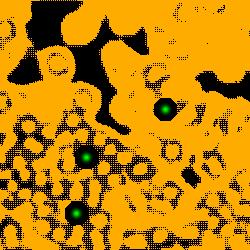

(a) image

(b) round 1

(c) round 2

(d) round 3

3.2 Self-training with background propagation

The detection performance of the initial model is not good enough because of the small number of labeled nuclei and large ignored areas. The unlabeled regions in images can be utilized to improve the performance by semi-supervised learning methods such as self-training. Intuitively, the initial model could predict the nuclei locations on the unlabeled regions. The predicted nuclei are then used to supervise the model training along with the originally labeled nuclei, like what the authors did on cell detection in [30]. However, we find that there are too many false positives among the newly detected nuclei because the trained model with the small number of labeled nuclei is not good. The false positives mislead the training during iterations, resulting in worse detection performance. Therefore, we propose an iterative learning strategy to refine the background map during self-training. Because the background tissue and blank areas are easier to be distinguished, producing less false positives.

The process of self-training is shown in Fig. 1(a). In each round of self-training, the background map is firstly obtained from the trained model of the previous round (or the initial model for the first round). Then the background map is combined with the original labeled points to generate a new mask for training. In background map generation, we select background pixels in the probability map if or . The first criterion is straightforward since is the probability of being nuclei. The second one is considered because many background pixels get predicted values close to 1, especially in the first stage. This behavior is expected because most background pixels are ignored during training. If the initialized model predicts them as nuclei pixels, the predictions will remain unchanged. In order to prevent from adding true positive into background, for case we only take into account the large connected components of areas greater than the average nuclei area, i.e., . The updated mask is finally generated by adding the new background information to the original extended Gaussian mask (See Eqn. 3).

| (3) |

An example is shown in Fig. 2 to illustrate the masks in different rounds of self-training. The foreground nuclei annotation (green pixels) is kept unchanged during the iterations while the background area (pixels in black) grows up gradually. In the third round, the background has high accuracy and the ignored pixels (orange) are almost all nuclei.